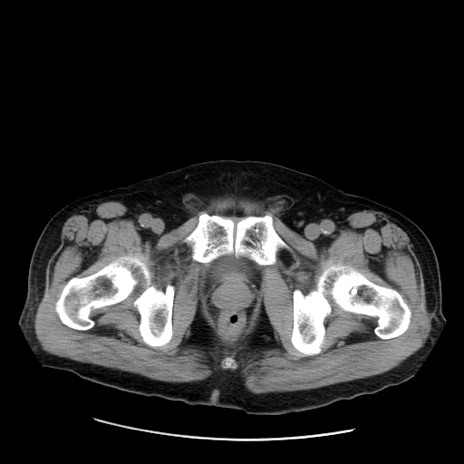

症例20(横断像)

【症例】 60歳代男性

【主訴】 腹部膨満、嘔吐

【現病歴】5日前頃より倦怠感を認め食事量減少し4日前の朝嘔吐、食事摂取困難となった。 3日前近医受診し点滴施行され整腸剤などを処方された。 当日他院を受診し、腹部膨満著明、炎症反応の上昇(CRP10.8、WBC11200)あり、紹介受診となる。

【身体所見】 意識JCS1 受け答えがはっきりしないBP 111/57mHg、 P 67bpm、、BT35.2°C、SpO2 97%(RA)、 腹部:膨隆、打診で鼓音あり、全体的に圧痛有り、腸蠕動音(-)、反跳痛ははっきりせず。

【データ】WBC 11400、CRP 14.20